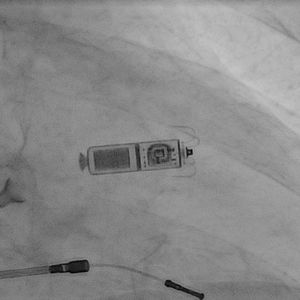

„Beiden Patienten geht es sehr gut mit dem neuen Kardiokapseln“, informierte der verantwortliche Oberarzt für Rhythmologie und interventionelle Kardiologie, Dr. Mathias Busch. Eine 86-jährige Frau und ein 82-jähriger Mann aus Greifswald profitierten von dem neuen System, das in beiden Fällen zur sofortigen Verbesserung der gesundheitlichen Zustandes führte. „Die 25,9 mm große Kardiokapsel ist weniger als ein Zehntel so groß wie ein herkömmlicher Schrittmacher und etwa so groß wie eine große Vitamintablette. Sie bietet die fortschrittlichste Herzschrittmachertechnologie und ist dabei kosmetisch unsichtbar und klein genug, so dass wir sie über einen Katheter minimalinvasiv unmittelbar ins Herz einbringen können“, erläuterte Busch.

Sobald die Kardiokapsel positioniert ist, wird sie an der Herzwand befestigt und kann bei Bedarf verlagert oder wieder entfernt werden. Im Gegensatz zu herkömmlichen Schrittmachern sind bei der Kardiokapsel weder Drähte (Elektroden) erforderlich, noch muss operativ unter dem Schlüsselbein eine Tasche unter der Haut angelegt werden. Stattdessen wird das System mit winzigen Titanärmchen in der Herzwand verankert und gibt über einen Pol an der Spitze des Geräts die elektrischen Impulse für die Herzaktivität ab. Trotz der geringen Größe der Kardiokapsel beträgt die geschätzte Lebenszeit der Batterie zehn Jahre. Die Micra Kardiokapsel ist für Patienten vorgesehen, die ein Einkammerstimulationssystem benötigen.